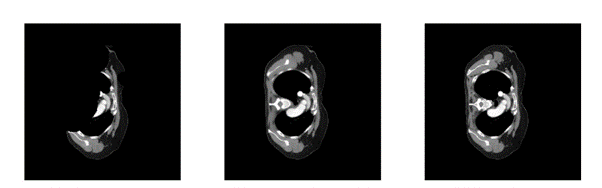

En af de tre cases gik ud på at fikse ødelagte CT-scanninger.

I billedet nedenfor ses et eksempel på, hvordan en model PER-teamet udviklede under konkurrencen kunne udfylde de manglende områder i en ødelagt CT-scanning.